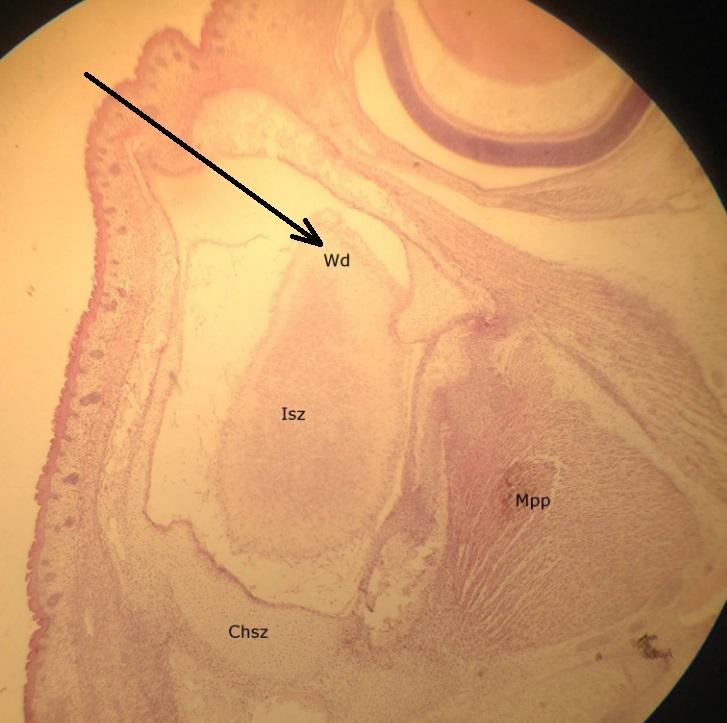

Pytanie 352

tęczówka (preparat rozwojowy z głowy szczura, zawiązek oka)